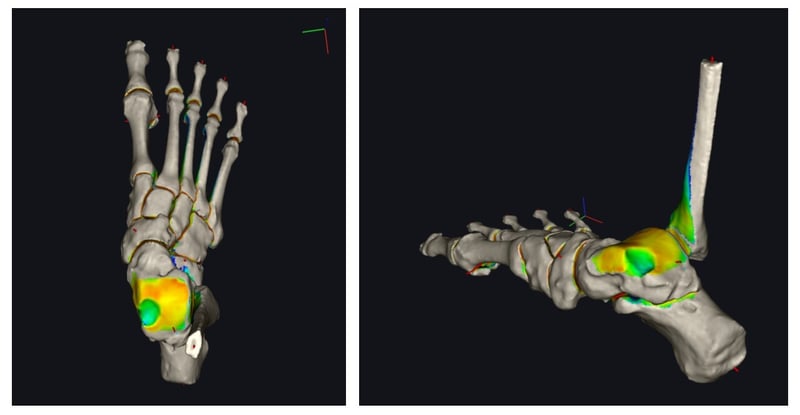

La TAC in carico, infatti, offre la possibilità di ottenere una misura affidabile della lesione, ma anche di andarne a misurare la reale forma, grazie a strumenti associati a intelligenza artificiale. Apprezzare la forma della lesione permette di essere ancora più precisi e di scegliere la tecnica che permetta la ricostruzione anatomica più efficace associando tecniche diverse di rigenerazione in base al caso.

Il nostro gruppo ha avviato questo filone di ricerca descrivendo come andare ad individuare la forma della lesione, misurarne l’area e guidare il paziente ed il chirurgo nella scelta terapeutica.

Efrima B, Dahmen J, Barbero A, Benady A, Maccario C, Indino C, Kerkhoffs G, Usuelli FG. Enhancing precision in osteochondral lesions of the talus measurements and improving agreement in surgical decision-making using weight-bearing computed tomography and distance mapping. Knee Surg Sports Traumatol Arthrosc. 2024 Jul;32(7):1871-1879. doi: 10.1002/ksa.12172. Epub 2024 Apr 9. PMID: 38591657.